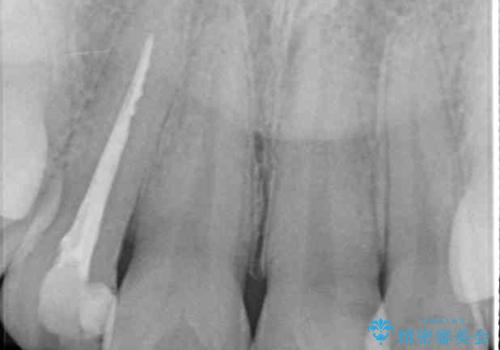

- 根管治療はやり直さずに、ファイバーポストを使用した土台を植立して、オールセラミッククラウンにて補綴することとしました。

神経を取り除いた歯の変色は、クリーニングやホワイトニングでは改善できないため、オールセラミッククラウンなどによる補綴治療が必要となります。